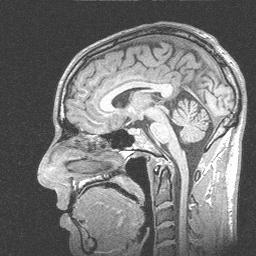

Sagittal view

Sagittal view

During the summer of 2000, I participated in an fMRI (functional magnetic resonance imaging) study at the University of Virginia. An fMRI scan shows not only the structure of the brain, but which parts are currently active. By asking people to do different things while being scanned, psychologists are able to figure out which parts of the brain are used for different tasks.

Since I was working with the psychologists at the time, I was not paid to participate in the study. However, I volunteered to do it anyway in order to help out my friends, advance mankind's knowledge, and get really cool pictures of what my brain would look like if my head were chopped in half. Enjoy!

Sagittal view

Sagittal view